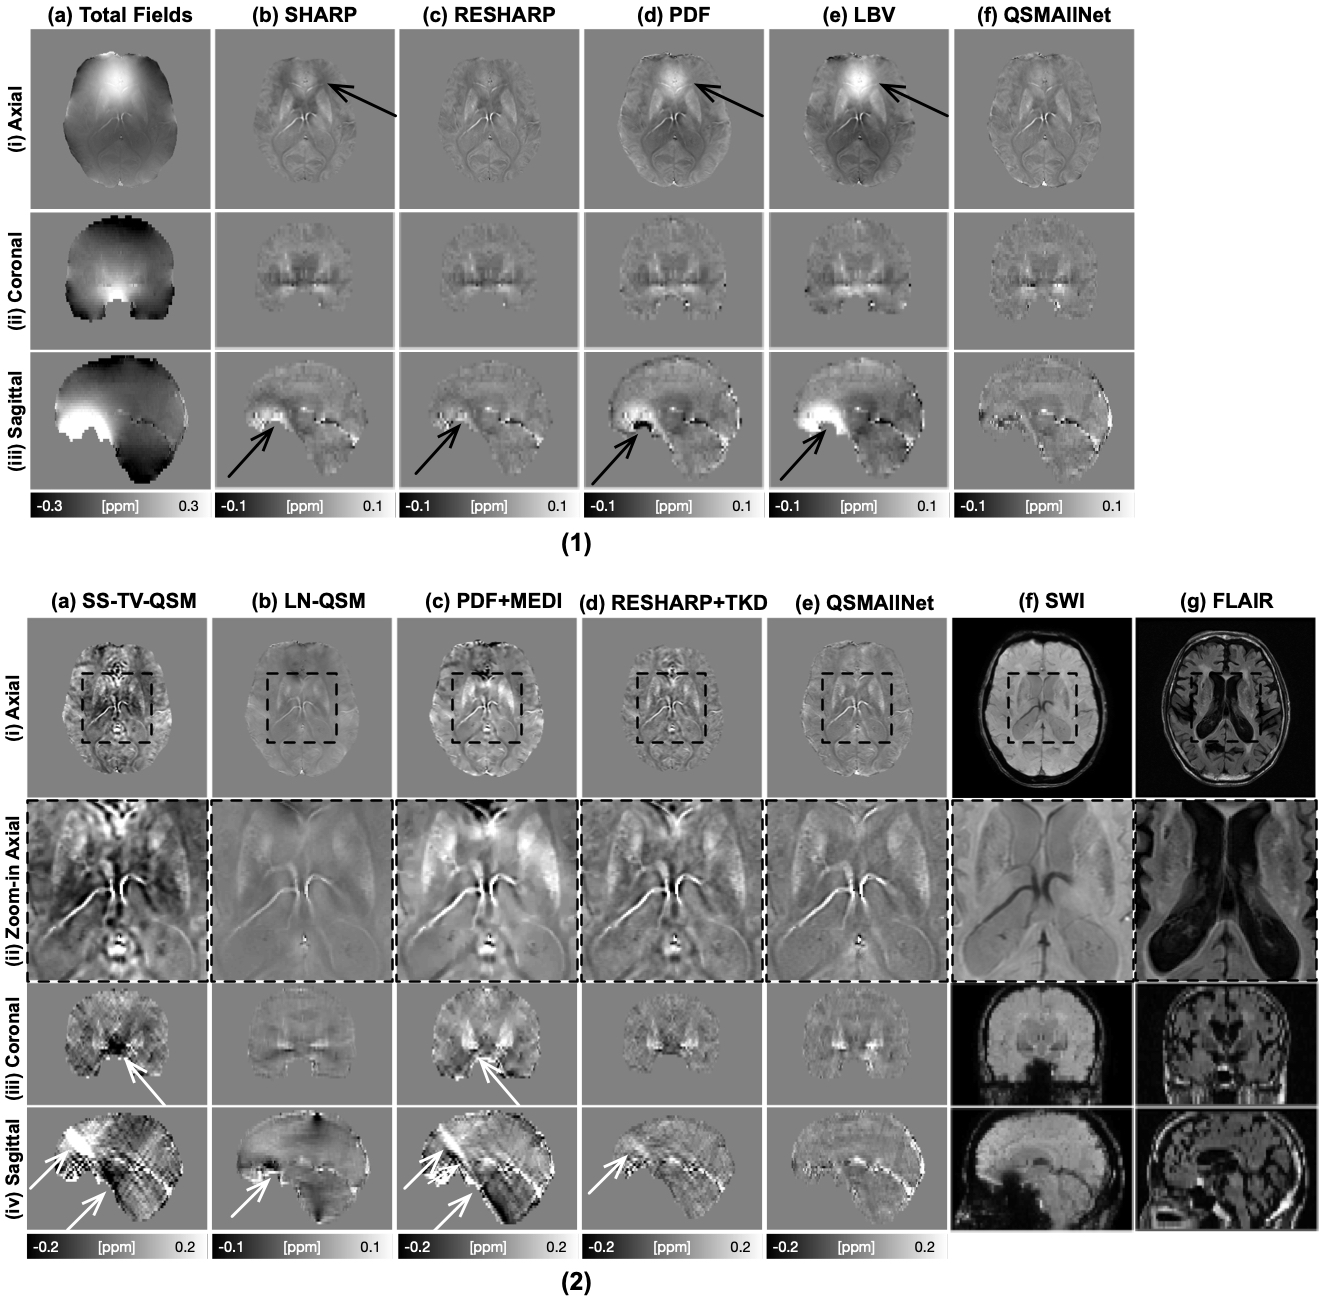

In Fig. 9, background removal results and susceptibility images of a 28-year-old subject with left mesial temporal lesion and Neurofibromatosis Type-1 is illustrated. Residual background field is visibile in SHARP, RESHARP, PDF, and LBV results (black arrows, 1, b-e, i-iii). PDF and LBV results show obvious shading artifacts (1, d-e, i-iii). QSMAllNet shows invisible artifacts in the local field. From the QSM images, SS-TV-QSM, PDF+MEDI, and RESHARP+TKD suffers severe shading artifacts and streaking artifacts, as shown (2, a, c, d, i-iv). LN-QSM shows strong shading artifacts, as shown (2, b, i-iv). With comparison to other methods, QSMAllNet results (2, e, i-iv) showed improved image sharpness, clear tissue structures, and no shading and streaking artifacts around bleeding regions.

Figure 9: Total fields and QSM background removal results (1), susceptibility images, SWI images and FLAIR images (2) on a 28-year-old subject with left mesial temporal lesion and Neurofibromatosis Type-1. In (1), residual background fields are clearly visible in SHARP, RESHARP, PDF and LBV (b-d) results in axial and saggital views. SHARP and RESHARP results (b-c) have brain erosion. LBV and PDF have shading artifacts in the tissue fields. QSMAllNet results show better background field removal. From the susceptibility maps (2), SS-TV-QSM, LN-QSM, PDF+MEDI, and RESHARP+TKD have susceptibility large estimation errors, especially streaking artifacts and shading artifacts (white arrows). Based on visual comparison, QSMAllNet can produce improved local field and susceptibility estimation.